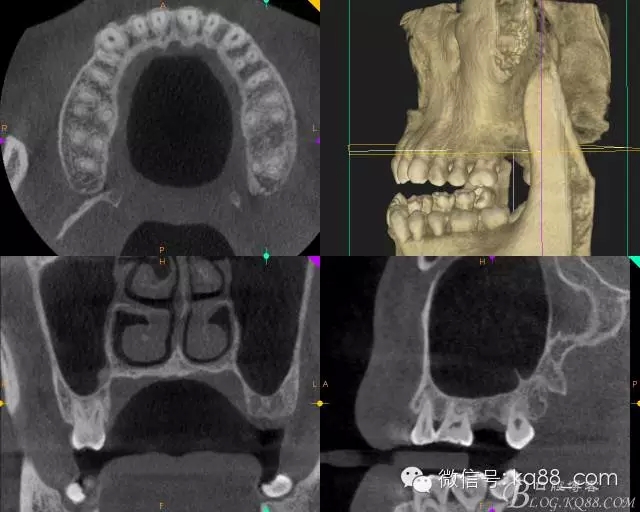

術(shù)前拍攝CT發(fā)現(xiàn)該處牙槽骨高度不足需要進(jìn)行內(nèi)提升手術(shù),但是 CT上看骨的寬度很好,所以決定采用微創(chuàng)植入。

術(shù)前的CT影像